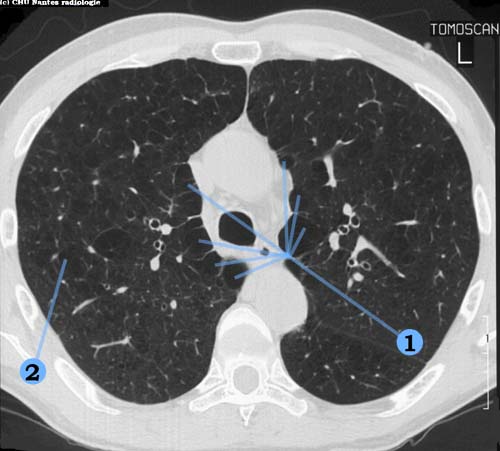

Emphysème pulmonaire débutant

coupe TDM en fenêtre parenchymateuse

1 . aspect hérissé de l'interface plèvre-poumon lié à l'existence de bulles d'emphysème sous pleurales

2 . emphysème pulmonaire avec de multiples zones d'hyperclartés parenchymateuses bilatérales ( aériques ) disséminées